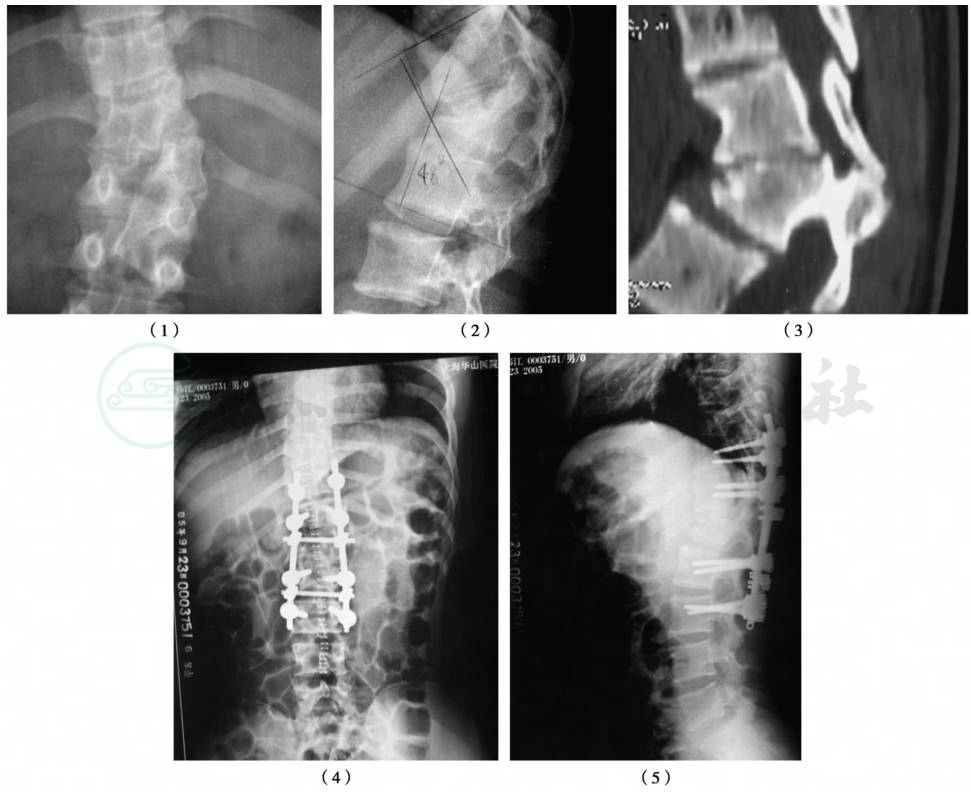

图2 半椎体切除融合内固定术

(1)X线正位片;(2)X线侧位片;(3)CT片;(4)术后X线正位片;(5)术后X线侧位片